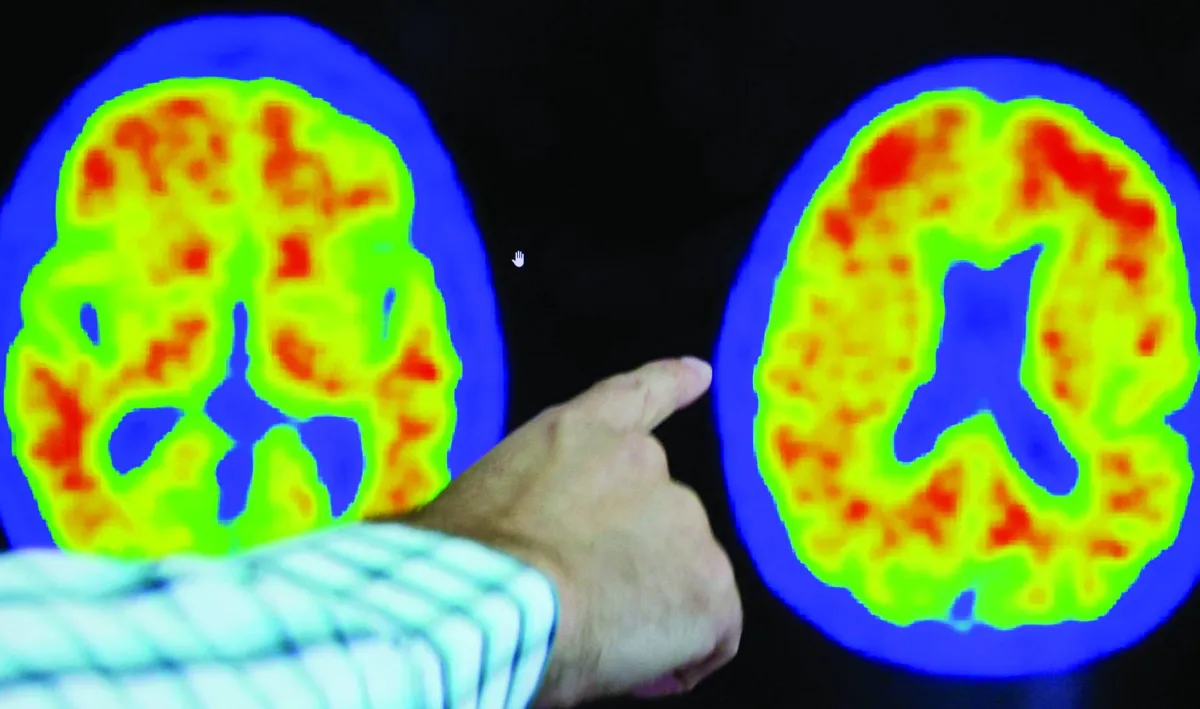

أصبح السعي لإيجاد علاج لمرض ألزهايمر مسعى تنافسياً ومثيراً للجدل بشكل متزايد؛ حيث شهدت السنوات الأخيرة العديد من الدراسات التي حاولت البحث في هذا الأمر.

وفي يوليو (تموز) 2022، أفادت مجلة «ساينس» بأن ورقة بحثية رئيسية نُشرت عام 2006 في مجلة «نيتشر» المرموقة، وحددت نوعاً فرعياً من بروتين الدماغ يُسمى «بيتا أميلويد» سبباً لمرض ألزهايمر، ربما كانت مبنية على بيانات مُلفّقة.

ولا يزال الباحثون يتخبطون في سعيهم لإيجاد علاج لما يُمكن اعتباره أحد أهم الأمراض التي تواجه البشرية.